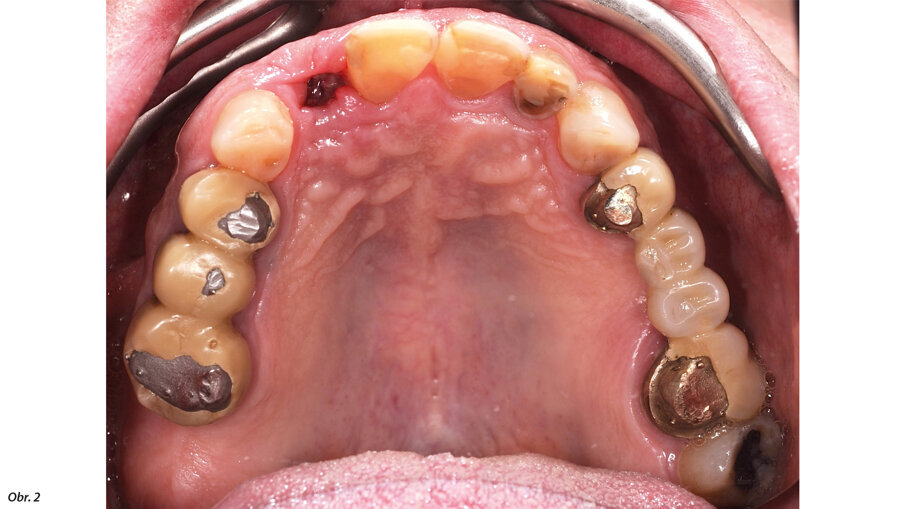

66letý pacient s non-inzulin dependentním diabetes mellitus a ischemickou chorobou srdeční se dostavil na ošetření parodontálního abscesu v oblasti radix relicta 12 a vícečetných fraktur stávajících náhrad (obr. 1–6). Během návštěvy byla zjištěna značná malokluze a ztráta VRO, abraze a fraktury stávajících náhrad i zbylých zubů a známky cervikální abfrakce. Pacient také trpěl mírnou bolestivostí svalů při palpaci, a to zejména v oblasti m. pterygoideus medialis et lateralis, sníženou schopností otevírání úst a slabými zvukovými fenomény v oblasti temporomandibulárních kloubů.